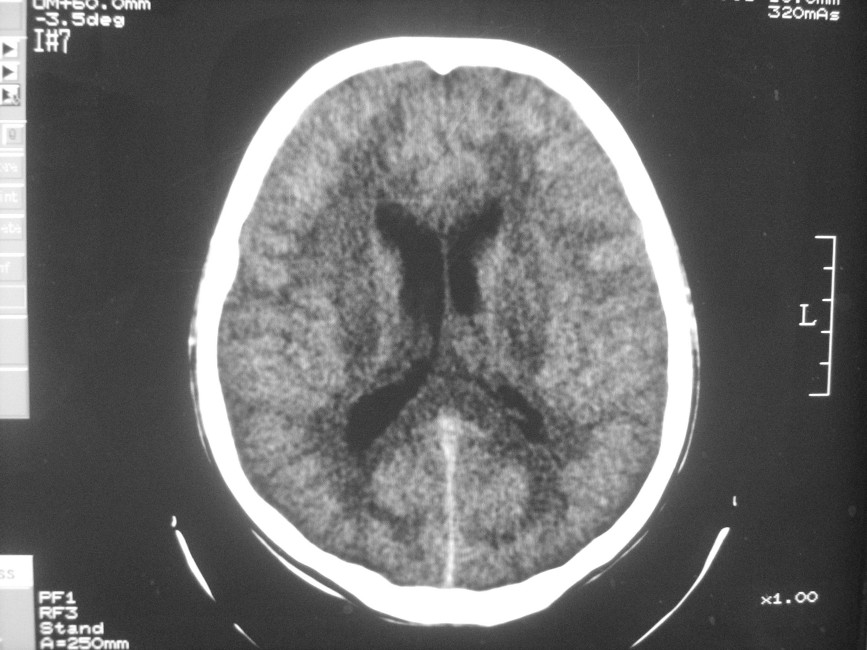

以下是引用zzyy在2008-6-16 10:13:00的发言:[br]两侧脑白质呈对称性密度减低,病儿有发热及脑膜刺激征。考虑急性病毒性脑炎。